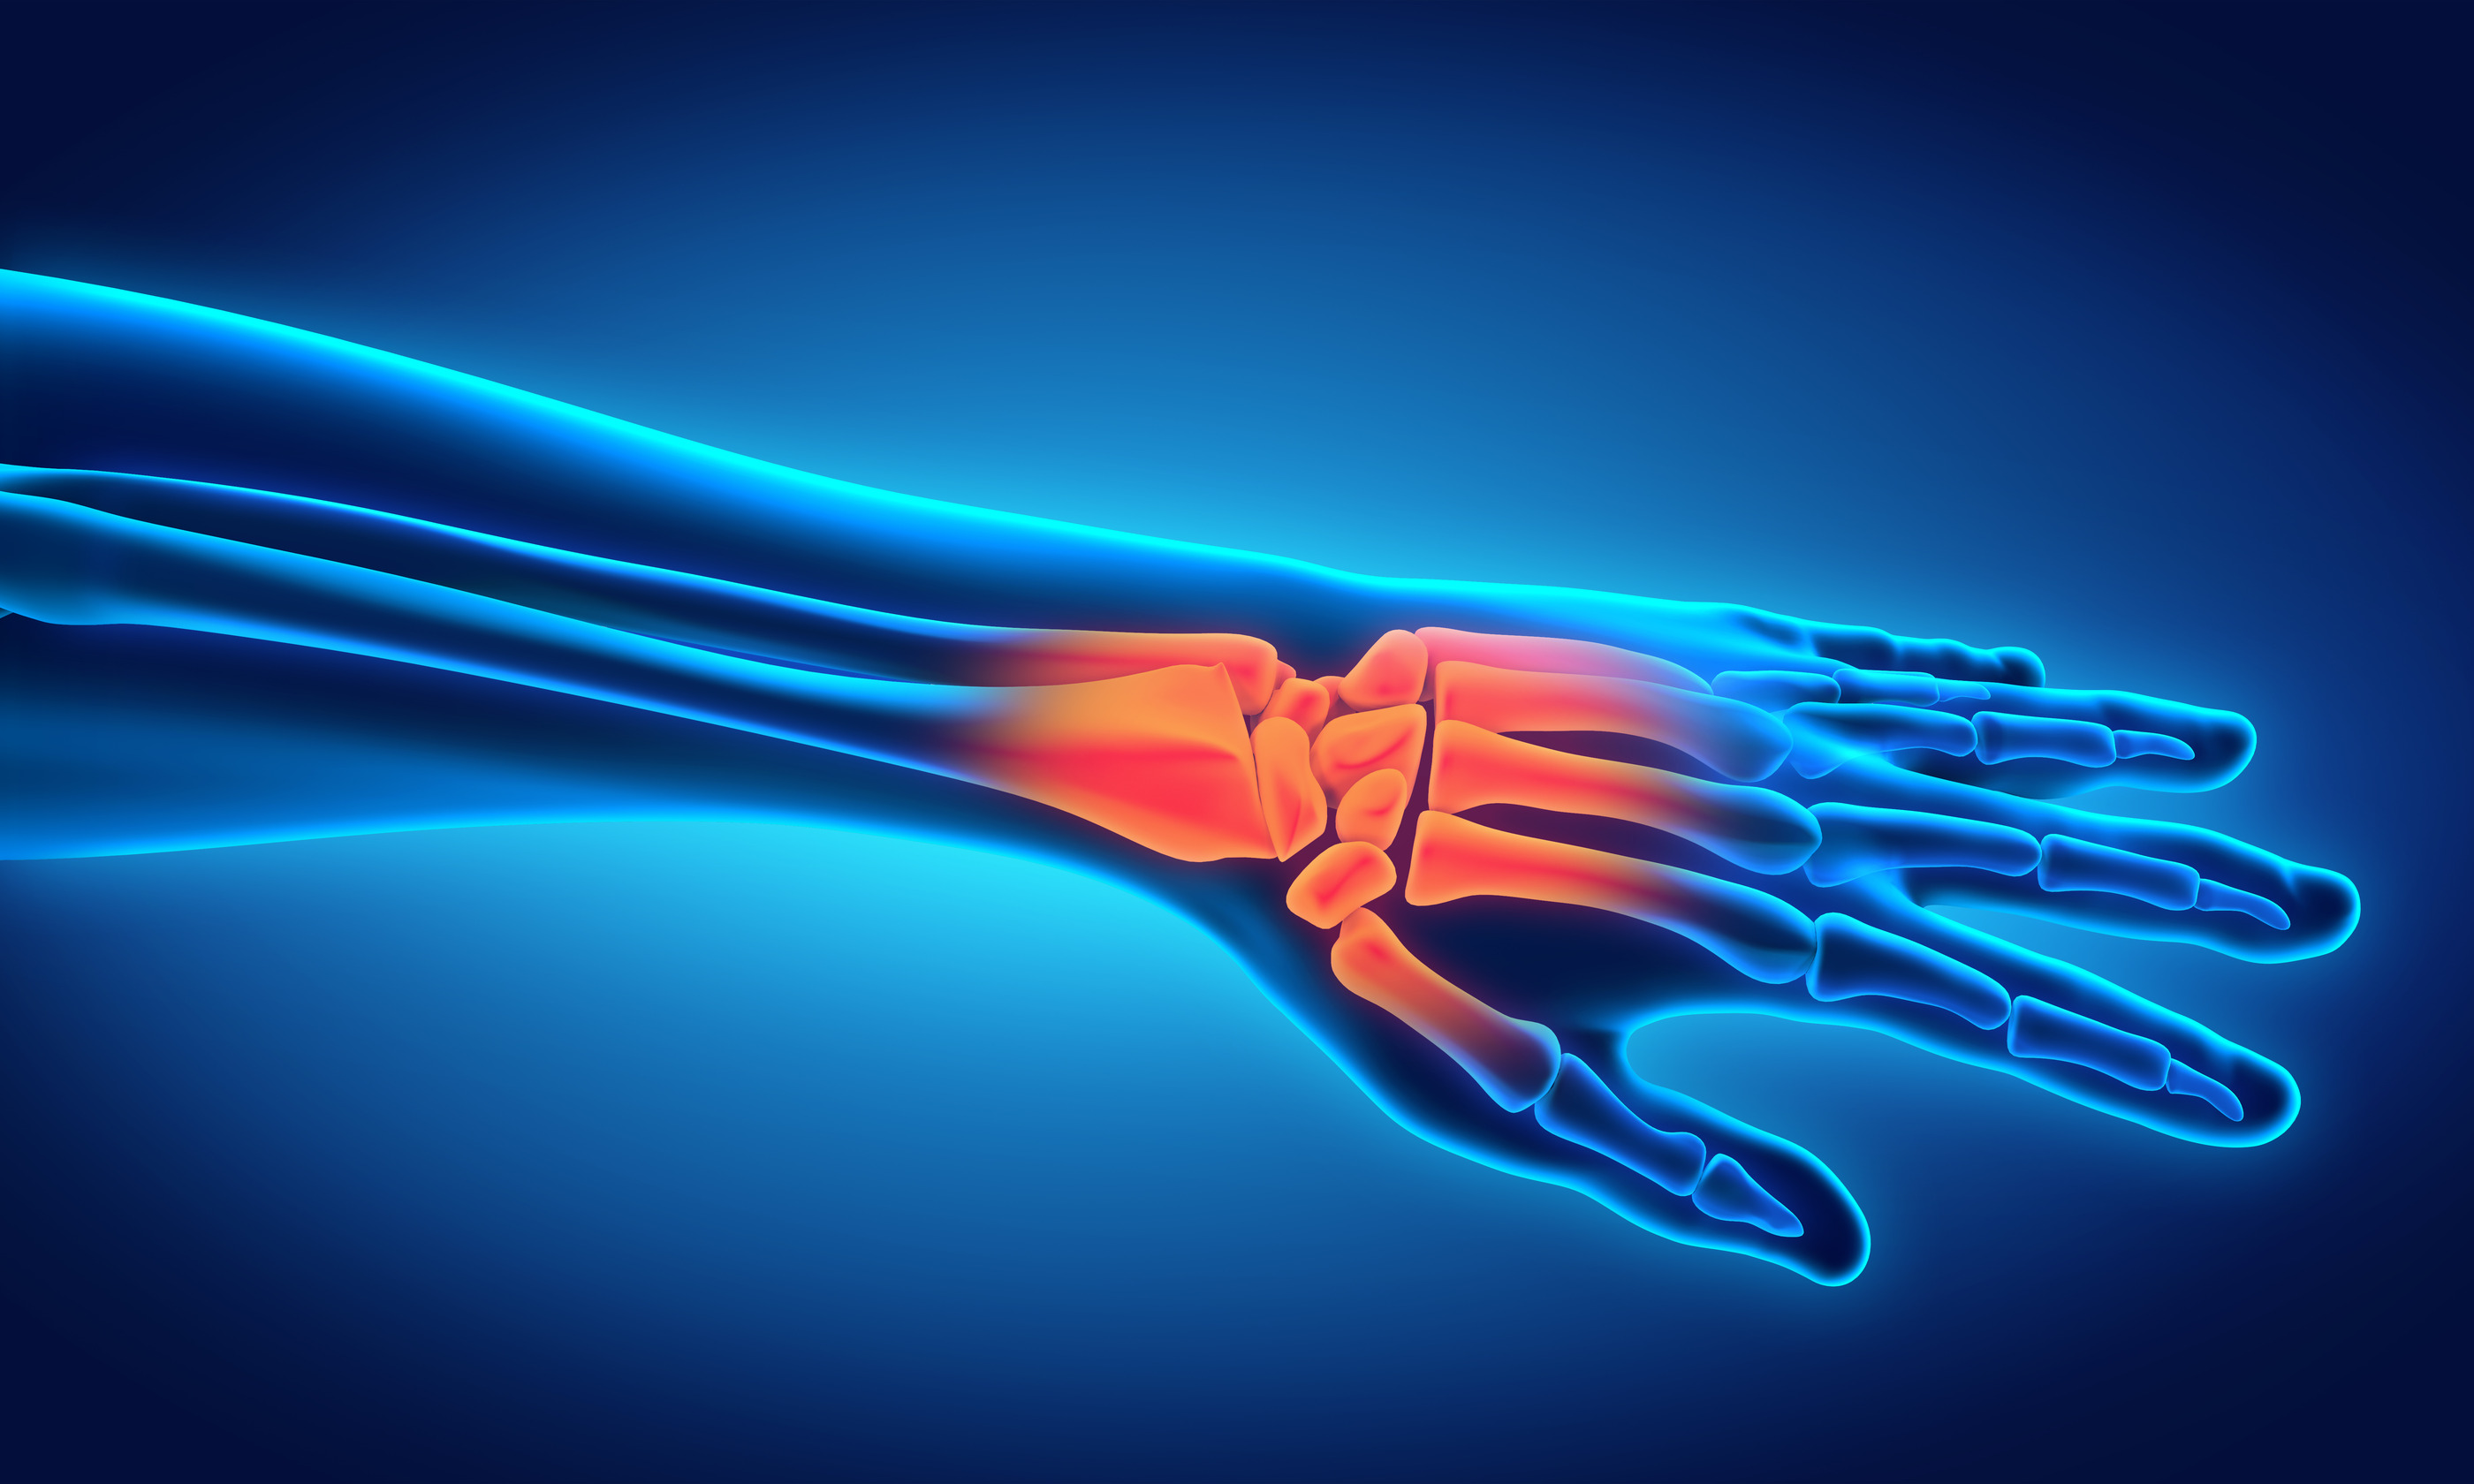

They’re made of an incredible network of bones, cartilages, nerves, connective tissues and muscles — all working together to perform some of the strongest and most intricate movements on a daily basis. And yet, they’re surprisingly delicate. When your hands and wrists hurt it often seems like you can’t focus on anything else.

Hand and wrist pain can be caused by overuse, traumatic injuries, arthritis and other disease processes. Treatments can include rest, anti-inflammatory medications, steroid injections, hand therapy or surgery.